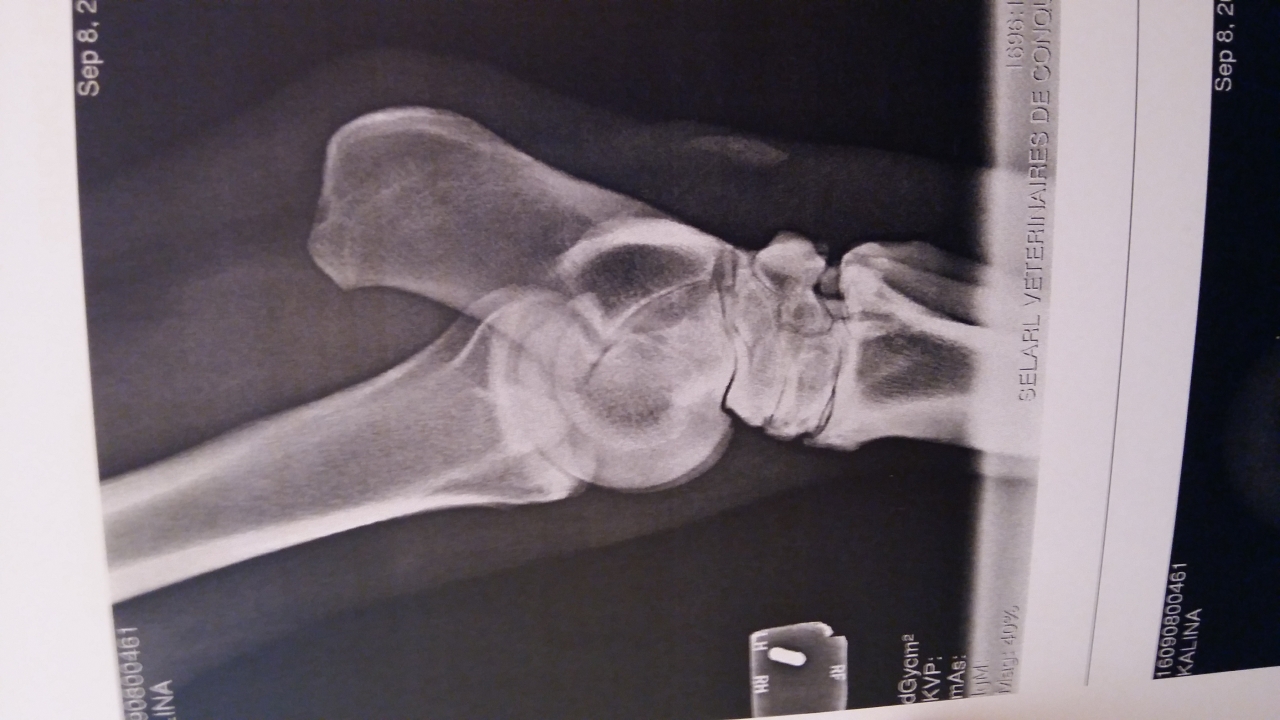

| Dire merci | Bonjour à tous ! J'ai amené ma jument de 18 ans à la clinique Lenormand pour des douleurs significatives sur l'antérieur droit et une tare molle sur le jarret gauche. pour la parenthèse cette tare molle est apparue en janvier suite à un mauvais coup. A l'époque le veto n'avait pas voulu faire de ponction et avait diagnostiqué un épanchement de synovie. Il n'y avait aucune douleur mais il y a quelques semaines j'ai noté douleur + augmentation de la taille de la tare Radios antérieurs Le veto s'est concentré sur les pieds uniquement parce que pour lui gros problème d'appui très visible à l'examen préliminaire. Je rappelle que ma jument est pieds nus. AG ![]() AD ![]() Radios postérieur gauche ![]() ![]() ![]() Bilan du véto Jument présentée pour une enflure en partie externe du jarret gauche. La distension implique la gaine tarsienne pas d'anomalie locomotrice, flexion négative. Boiterie AD sur cercle à main droite. La jument présente un aplomb AG avec des talons fuyants et un pied AD très légèrement encastelé. On note une diminution de l'appui sur l'AD. Radiographiquement on note une faible épaisseur de sole à G et à D. Présence de lésion d'éparvin marqué au niveau intarsien distal et tarso metarsien ainsi qu'une prolifération osseuse importante au niveau du sustentaculum tali. Echographiquement la prolifération osseuse vient en contact du tendon fléchisseur profond sans image de lésion du tendon visible. En conclusion distension de la gaine tarsienne G avec prolifération osseuse sur le sustentaculum tali à l'origine d'une tendinopathie chronique. Douleur aux pieds avec faible épaisseur de sole. Il est préférable de ferrer les antérieurs si la jument continue à avoir une activité. La gaine tarsienne a été infiltrée avec de la triacinolone. L'effet est probablement temporaire la distension devrait revenir plus ou moins rapidement en fonction de l'activité de la jument. Une intervention chirurgicale sous AG est possible [...] mais aujourd'hui elle ne présente aucune boiterie. |